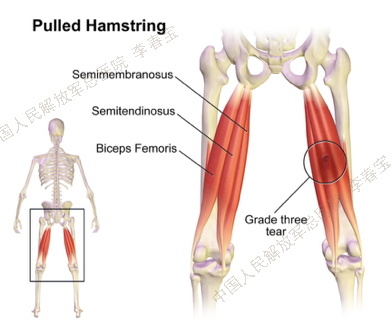

1. 腘绳肌腱损伤

腘绳肌位于大腿后侧,是主要的屈膝肌群,由股二头肌、半腱肌、半膜肌组成。这些肌肉共同的起点是坐骨结节。当髋、膝关节过伸或股四头肌过分用力时极易造成腘绳肌损伤,损伤多位于坐骨结节止点处。损伤后,当腘绳肌突然剧烈地收缩时,就会引发大腿后方突发、剧烈的疼痛,如果撕裂较严重,肌腹上可以摸到一个局部凹陷。治疗:经保守治疗无效,可考虑手术治疗。目前有开放手术和关节镜下微创手术两种选择。